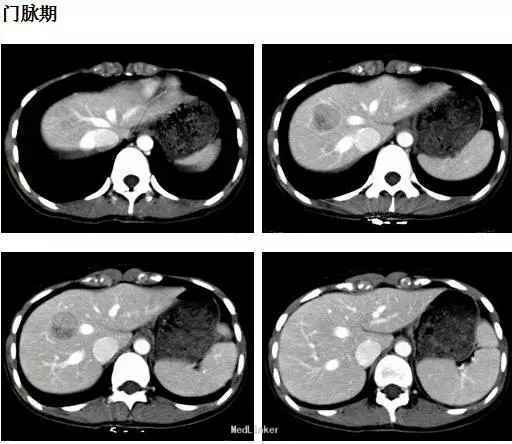

体检:腹平软,无肠型及蠕动波,未见腹壁静脉曲张,肝脾肋下未及,肝区无叩击痛,全腹无压痛、反跳痛、肌紧张。腹水征阴性。 CT表现:肝右前叶可见类圆形等低混杂密度影,边界尚清,直径约2.5cm,CT值-20~35HU,;增强后动脉期病灶呈结节样强化,门脉期病灶包膜强化更明显,有逐渐向中心填充趋势。

初步诊断:肝血管瘤。原拟定期复查,但患者强烈要求手术治疗,遂予肝部分切除术,术中所见也考虑血管瘤可能,术后恢复可。术后病理: 肝脏血管平滑肌脂肪瘤。免疫组化: melan-A(+)、HMB-45(+)、SMA灶性(+)、actin灶性(+)、S-100(-)、CK(-)、Desmin(-)、Ki-67阳性细胞约2%。